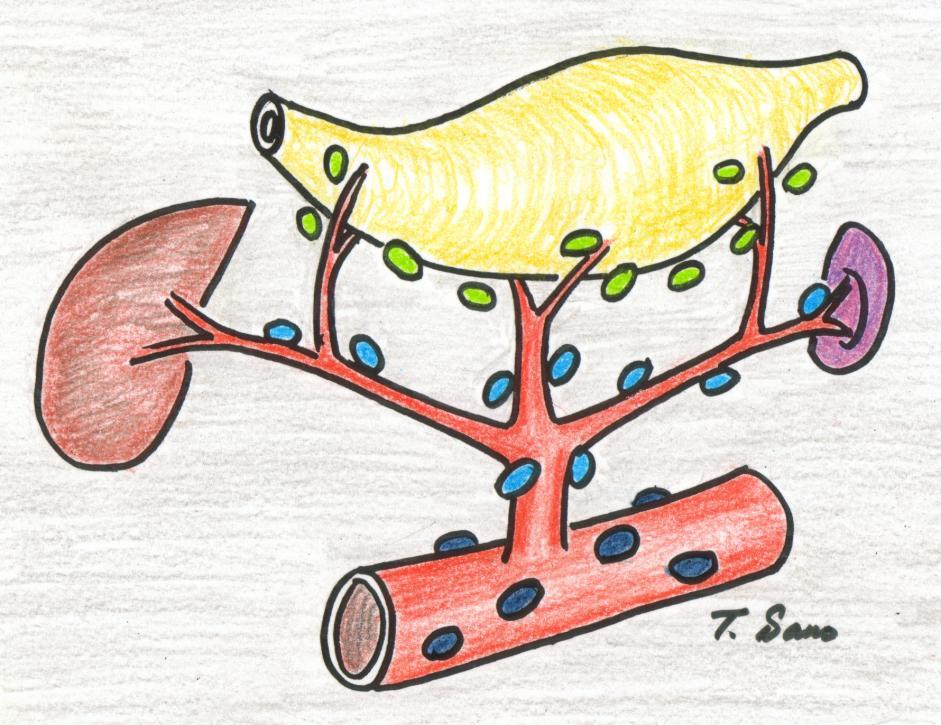

Níveis de metástases para linfonodos:

Nível D1 linfonodos perto do órgão acometido pelo câncer, D2 linfonodos nos ramos das artérias que levam sangue ao órgão com câncer, D3 linfonodos na origem das artérias principais. (associado à figura abaixo)